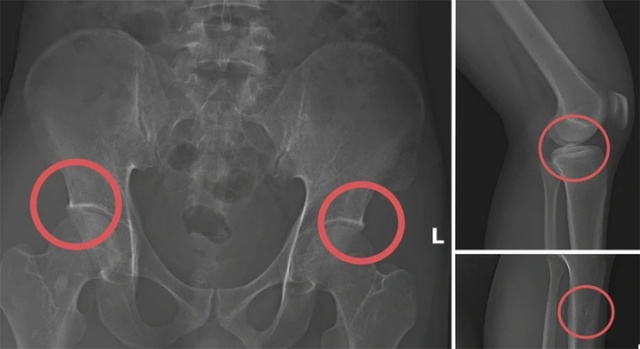

Các địa điểm được lựa chọn thường là khu vực vắng như hồ câu tại xã Cẩm Khê hoặc nhà riêng của một số đối tượng. Tại đây, Châu tiêm thuốc gây mê vào cơ thể những người tham gia rồi dùng búa tác động vào các vị trí như xương chậu hoặc xương đùi để tạo thương tích nặng. Đây được xem là thủ đoạn nguy hiểm trong vụ án Phú Thọ nhằm hợp thức hóa hồ sơ yêu cầu bồi thường.

Hình ảnh cho thấy các đối tượng tự gây thương tích nhằm trục lợi.